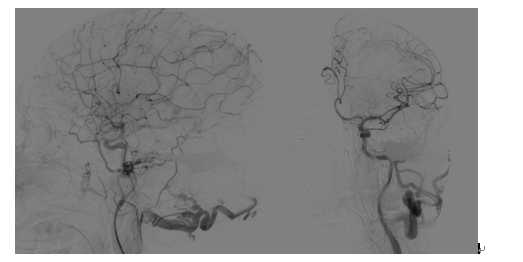

术中介入治疗后

该病人是一名42岁的黑龙江籍男性,长期在北京打工,9月1日突发剧烈头痛、右上肢偏瘫,就诊于天坛医院急诊科,行CT检查显示颅内左顶血肿,脑水肿明显;进一步完善CTA发现左侧异常迂曲增粗的巨大静脉及位于血肿中心的巨大球球瘤,双侧头皮颞浅动脉和枕动脉异常增粗,颅底脑膜广泛供血。急诊收入脑血管三病区,考虑脑膜脑动静脉瘘,病情复杂,同时颅内出血量大,颅内血管畸形情况不明确,手术风险极高,拟进一步完善造影检查再行手术治疗,给予脱水保守治疗。入院后第三天早上8时,病人突发意识障碍加重,左侧瞳孔扩大,光反应消失,正在科室讨论病情的赵继宗院士及张东主任医师查看病人,查体后考虑病人发生脑疝,需要急诊手术干预,迅速判断病情后,赵继宗院士和张东主任认为该病人非常适合进入复合手术室进行抢救,随后张东主任团队紧急联系手术室及神经介入科,组织相关医护团队转运病人至复合手术室,以最快的速度开始抢救,经降颅压、气管插管等紧急抢救后病情暂时平稳,病人瞳孔恢复正常。神经介入科杨新建主任团队接到通知后第一时间赶到手术室,首先进行脑血管造影,明确了巨大硬脑膜动静脉瘘的诊断,后使用弹簧圈和血管栓塞剂成功封堵瘘口,明显降低了开颅手术的风险。随后张东主任团队迅速进行开颅手术,在术中B超,和电生理监测下,成功清除脑内血肿,术中发现巨大静脉球瘤为出血责任部位,予以夹闭,同时行去骨瓣减压术,解除脑疝,最终手术历时10小时,顺利结束,病人平稳转运回重症监护病房,苏醒后意识水平及神经功能明显改善。术后经过科室医护团队的精心治疗与护理,病人于9月15日出院,出院时病人神清语利,双侧肢体肌力正常,无明显神经功能障碍,生活完全自理,拟6月后回院行颅骨修补手术。